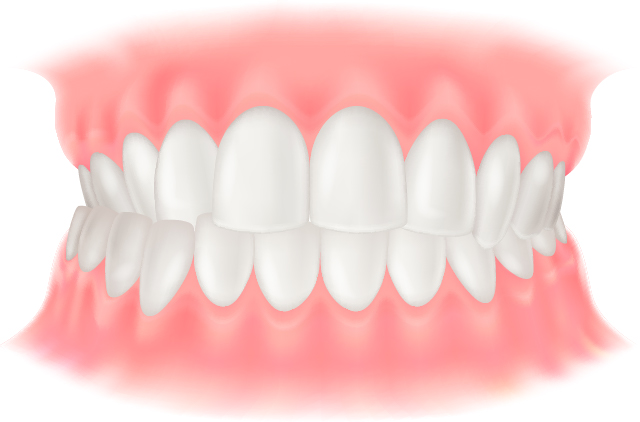

上顎前突(出っ歯)

上の歯が前方に傾斜して生えている状態、または下の歯全体が後方に位置することで出っ歯に見える状態です。唇を切ってしまったり、顔を強打した際に歯が折れやすくなることがあります。

下顎前突(受け口)

上の歯より下の歯が前方に出ている状態で、上顎が小さい、または下顎が大きいことで起こります。噛みにくさや滑舌の悪さにつながることがあります。

開咬

噛んでも前歯が噛み合わない状態です。発音が悪くなったり、前歯で噛み切ることが難しくなります。舌の癖や指しゃぶりが原因となることがあります。

叢生(ガタガタ)

歯がでこぼこに並んでいる状態です。歯みがきでブラシが届きにくく歯垢が残りやすいため、虫歯や歯槽膿漏の原因になります。

過蓋咬合

上の歯が下の歯を覆うほど深く噛んでいる状態です。下の歯が上の歯ぐきを刺激して口内炎ができたり、前歯が乾いて虫歯の原因になることがあります。

上下顎前突

上顎・下顎ともに前方へ突き出ている状態です。

交叉咬合

上下の噛み合わせが左右にずれている状態です。顎の成長差が生じ、顔の歪みにつながる場合があります。

空隙歯列(すきっ歯)

歯と歯の間に隙間がある状態で、顎の骨の大きさに対して歯が小さいことが原因です。食べ物が詰まりやすく、虫歯や歯周病の原因となるほか、息漏れによりサ行・タ行・ラ行の発音が悪くなることがあります。